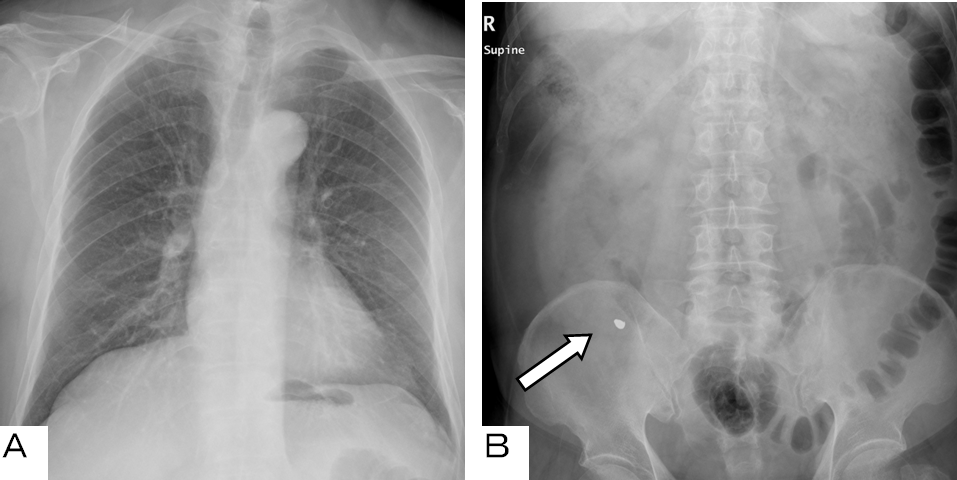

An 80-year-old male was referred to our hospital after he aspirated a tooth into his airway during a dental procedure. An 8-mm radiopaque foreign body was detected in the left lower bronchus on a chest radiograph and computed tomography scan (Figure 1) and (Figure 2). Removal by flexible bronchoscopy was attempted on the next day, but the foreign body was not found in either bronchial tree. The radiograph showed the tooth in the abdomen (Figure 3). The tooth was considered to have been expectorated and swallowed into the digestive tract. He was discharged, and one week later, we confirmed that the patient passed it.

Figure 1: An 8-mm radiopaque foreign body is seen in the left lower bronchus on a chest radiograph.

Figure 3: (A, B) During bronchoscopy on the next day after admission, the foreign body is not seen on a chest radiograph. The radiopaque foreign body appears in the abdomen. It passed through the patient’s digestive tract one week later.